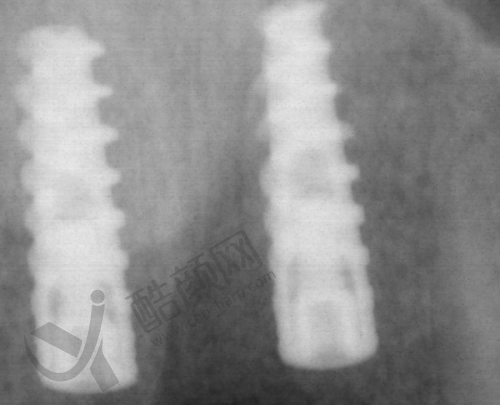

一般来说,种植体的品牌不同,价格也会有较大差异。一些有名进口品牌的种植体,由于其质量和稳定性较好,价格自然就高。而牙冠的材质也有多种选择,比如烤瓷牙冠、全瓷牙冠等,不同材质价格也不一样。手术费则和医生的技术水平、手术的复杂程度有关。检查费包括口腔CT、X光等,这些都是确保手术顺利进行的必要环节。

第三,询问种植体的品牌和质量。虽然是低价种植牙,但也不能忽视种植体的质量。要详细了解种植体是哪个品牌的,有没有质量认证。正规的种植体都会有相关的说明书和质量确保。同时,要注意种植体的产地,一般来说,一些发达国内的种植体质量相对更有保护。